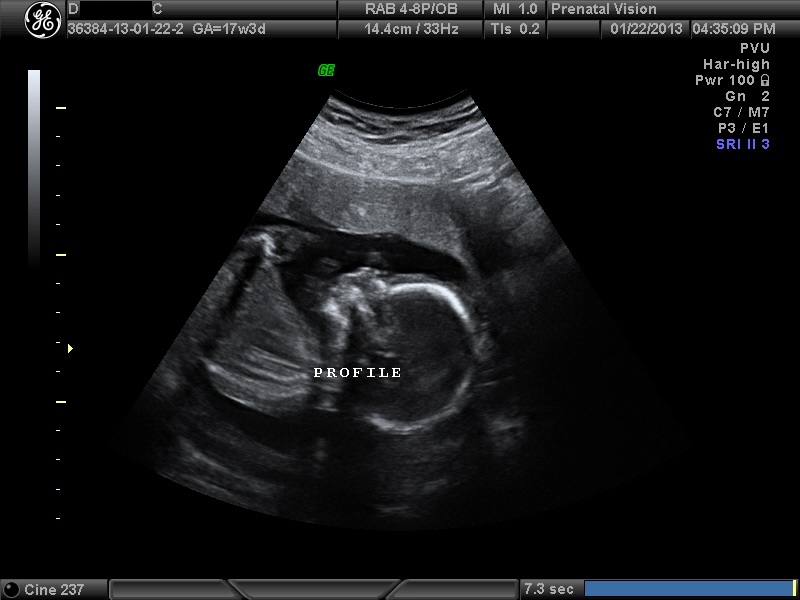

IMAGES_5 January 22, 2013 by Courtney Leave a comment ← Previous Image Next Image → 17w3d Like Loading...